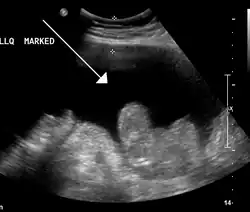

Ascites in a person with abdominal cancer as seen on ultrasound

Ultrasound investigation is often done before attempts to remove fluid from the abdomen. This may reveal the size and shape of the abdominal organs, and Doppler studies may show the direction of flow in the portal vein, as well as detecting Budd–Chiari syndrome (thrombosis of the hepatic vein) and portal vein thrombosis. The sonographer also can estimate the amount of ascitic fluid, and difficult-to-drain ascites may be drained under ultrasound guidance. An abdominal CT scan is more accurate than a sonogram to reveal abdominal organ structure and morphology.[13]